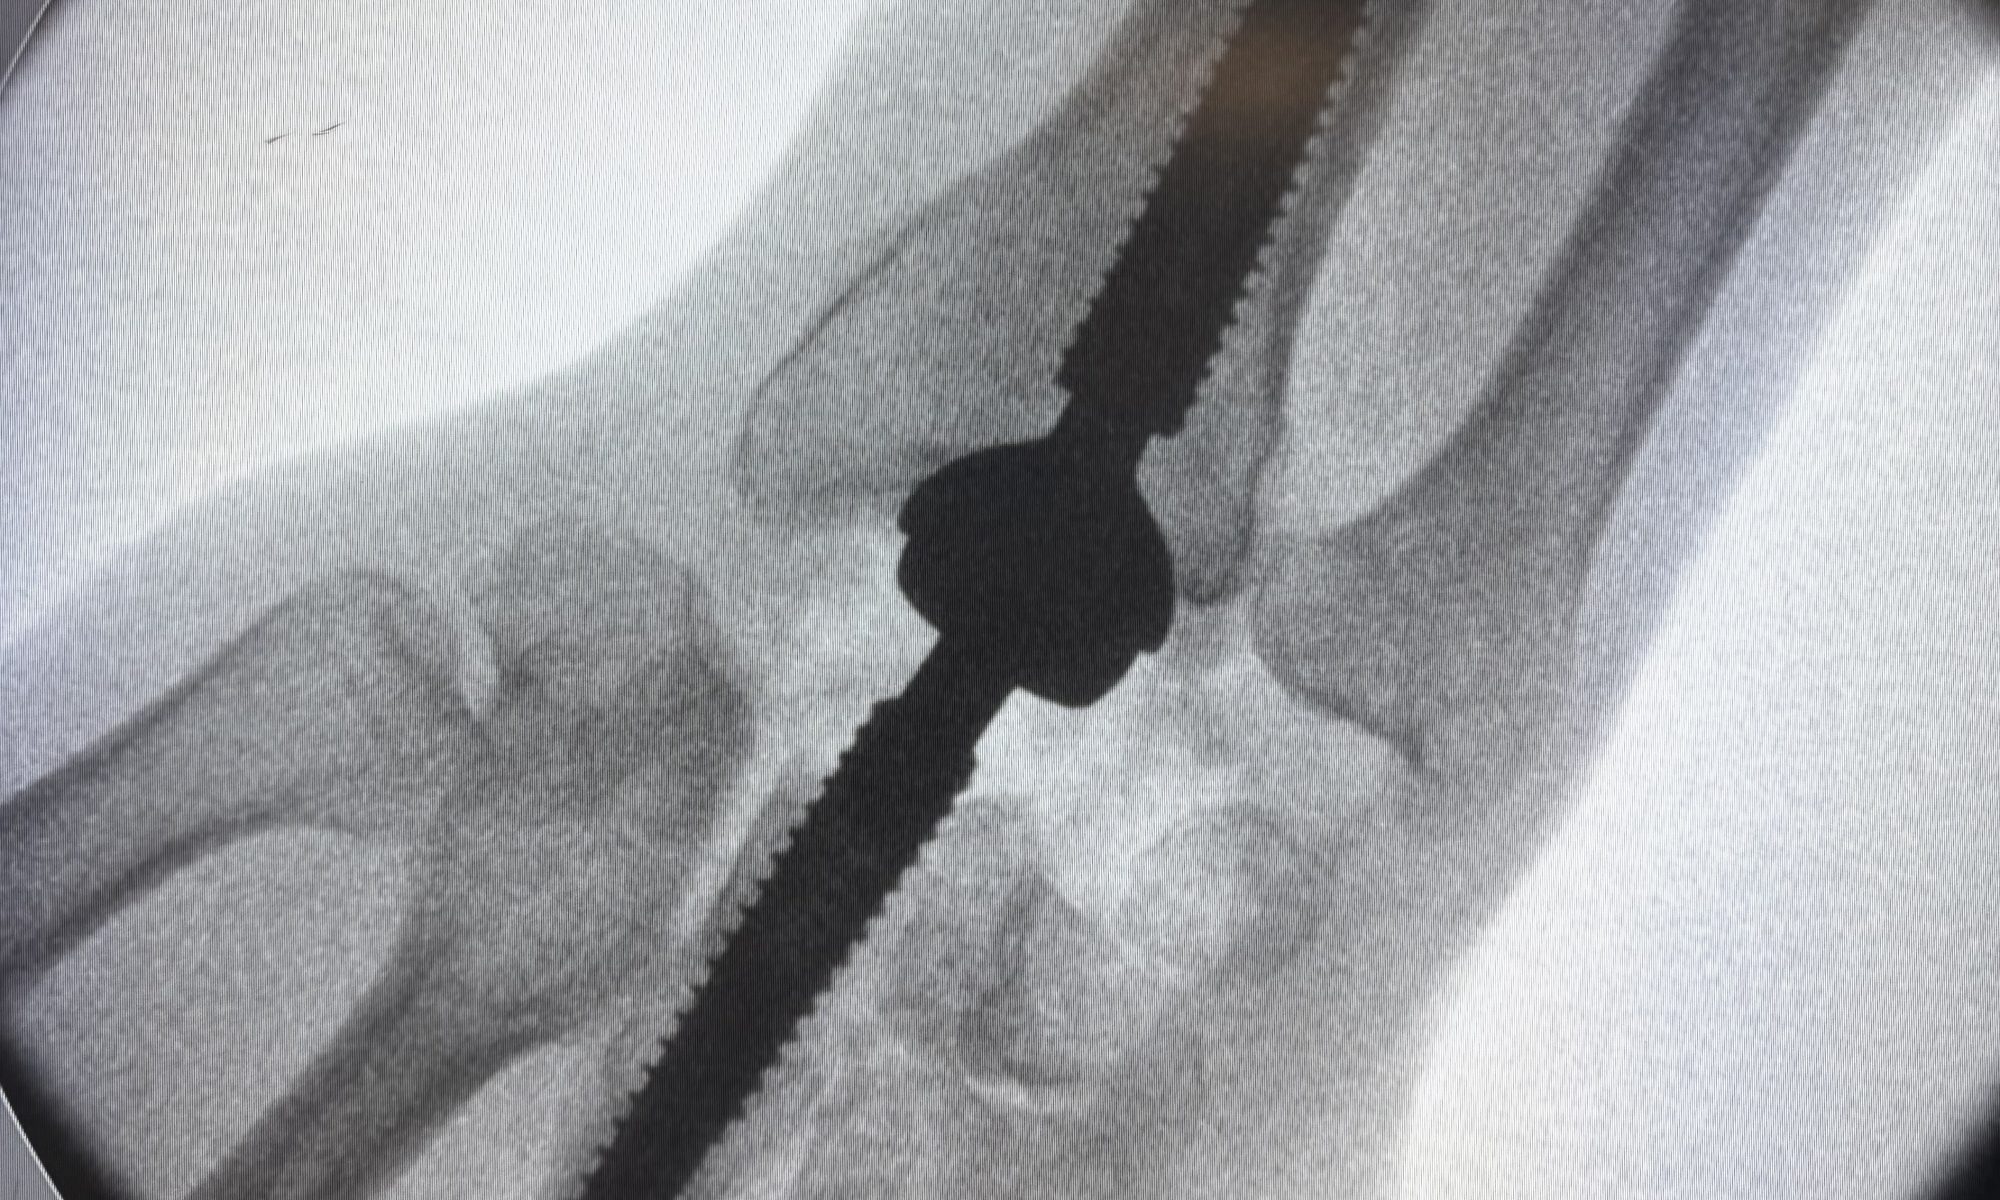

Qu’est-ce qu’une prothèse totale de poignet ?

La prothèse totale de poignet est un implant médical destiné à remplacer une articulation du poignet sévèrement usée.

Elle est composée de plusieurs éléments artificiels permettant de restaurer une articulation fonctionnelle, tout en limitant la douleur.

Quels types de prothèses de poignet existent ?

Il existe aujourd’hui différents modèles de prothèses totales de poignet, utilisés en France.

Certains implants sont développés par des fabricants spécialisés comme Keri Médical, parmi d’autres dispositifs disponibles.

Le choix de la prothèse repose uniquement sur des critères médicaux :

• Qualité de l’os

• Morphologie du poignet

• Pathologie sous-jacente

• Expérience du chirurgien

Il n’existe pas de prothèse universelle : chaque situation est évaluée individuellement.